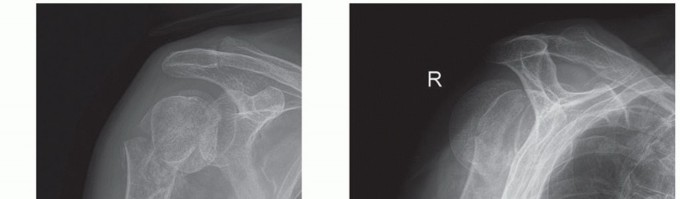

Proximal humerus fractures involve isolated or combined injuries to the greater tuberosity, lesser tuberosity, articular segment, and proximal humeral shaft. Overall, proximal humerus fractures account for 4% to 5% of all fractures.2,8,11,13 ## ANATOMY The proximal humerus consists of four segments: the greater tuberosity, lesser tuberosity, articular segment, and humeral shaft (FIG 1). The most cephalad surface of the articular segment is, on average, 8 mm above the greater tuberosity.18 Humeral version averages 29.8 degrees (range, 10 to 55 degrees).18,23 The intertubercular groove lies between the tuberosities and forms the passageway for the long head of the biceps as it traverses from the intra-articular origin into the distal arm. The tuberosities attach to the articular segment at the anatomic neck. The greater tuberosity has three facets for the corresponding insertions of the supraspinatus, infraspinatus, and teres minor tendons; the lesser tuberosity has a single facet for the subscapularis. The deltoid, pectoralis major, and latissimus dorsi all insert on the humerus distal to the surgical neck. These soft tissue attachments contribute to the deforming forces sustained with proximal humerus fractures. Illustration 1 for Hemiarthroplasty for Proximal: Effective Treatment for Fractures --- Illustration 2 for Hemiarthroplasty for Proximal: Effective Treatment for Fractures ### FIG 1 • Neer classification of proximal humerus fractures: 1, greater tuberosity; 2, lesser tuberosity; 3, articular surface; 4, shaft. The humeral head receives its blood supply from the antero-lateral branch of the anterior humeral circumflex artery (the arcuate artery of Laing) and the posterior humeral circumflex artery. The artery of Laing courses parallel to the lateral aspect of the long head of the biceps and enters the humeral head at the interface between the intertubercular groove and the greater tuberosity.20 More recent studies have indicated that the posterior branch may play a larger role in perfusion of the fractured humeral head, reducing the risk of osteonecrosis.10,15,16 ## PATHOGENESIS The incidence of proximal humerus fractures is increasing with an aging population and associated osteoporosis. The mechanism of injury may be indirect or direct and secondary to high-energy collisions in younger patients (eg, motor vehicle accidents, athletic injuries) or falls from standing height in elderly patients. Pathologic fractures from primary or metastatic disease should be included in the differential diagnosis. Risk factors for the development of proximal humerus fractures in the elderly patient population include low bone density, lack of hormone replacement therapy, previous fracture history, three or more chronic illnesses, and smoking.17 ## NATURAL HISTORY Neer's classic study in 1970 compared the results of nonoperative treatment with hemiarthroplasty for three-and fourpart displaced proximal humerus fractures. No satisfactory results were found in the nonoperative group owing to inadequate reduction, nonunion, malunion, and humeral head osteonecrosis with collapse.22 Stableforth28 reaffirmed this in a study in which patients were randomized to nonoperative management or prosthetic replacement. The patients with displaced fractures treated nonoperatively had worse overall results for pain, range of motion, and activities of daily living. Olerud et al25 most recently demonstrated significantly improved quality of life with a trend toward pain scores with four-part fractures treated with hemiarthroplasty versus observation. ## PATIENT HISTORY AND PHYSICAL FINDINGS A thorough history and complete physical examination should be performed. History should include mechanism of injury, premorbid level of function, occupation, hand dominance, history of malignancy, and ability to participate in a structured rehabilitation program.14 Illustration 3 for Hemiarthroplasty for Proximal: Effective Treatment for Fractures --- Illustration 4 for Hemiarthroplasty for Proximal: Effective Treatment for Fractures ### FIG 2 • A. Anteroposterior (AP) and (B) scapular “Y” views of a displaced four-part proximal humerus fracture without evidence of concomitant dislocation. (Copyright Kamal I. Bohsali, MD.) A review of systems should involve queries regarding loss of consciousness, paresthesias, and ipsilateral elbow or wrist pain. On physical examination, the orthopaedic surgeon should look for swelling, soft tissue injuries, ecchymosis, and deformity. Posterior fracture-dislocations will demonstrate flattening of the anterior aspect of the shoulder with an associated posterior prominence. Anterior fracture-dislocations present with opposite findings.14 ## IMAGING AND OTHER DIAGNOSTIC STUDIES Appropriate radiographs include biplanar views of the shoulder14 (FIG 2). If the axillary view cannot be obtained because of patient discomfort, alternate views such as the Velpeau trauma axillary view can be used to evaluate and classify the glenohumeral articulation.2 The Neer classification is based on the four anatomic segments of the proximal humerus: the humeral head, the greater and lesser tuberosities, and the humeral shaft (see FIG 1).11 Number of parts is based on 45 degrees of angulation or 1 cm of displacement from neighboring segments. The AO/ASIF/OTA Comprehensive Long Bone Classification system distinguishes the valgus impacted fourpart proximal humerus fracture from other four-part fractures with partial preservation of the vascular inflow to the articular segment through an intact medial capsule.8,19,26 The current fracture classification systems have fair interobserver reliability, even with the addition of computed tomography (CT) scans. Despite the limitations of these systems, they remain clinically useful when deciding on nonoperative versus operative treatment.2,11 CT scans may be helpful in evaluating tuberosity displacement and articular surface involvement.12,14 ## DIFFERENTIAL DIAGNOSIS Acute hemorrhagic bursitis Traumatic rotator cuff tear Simple dislocation Acromioclavicular separation Calcific tendinitis2 ## NONOPERATIVE MANAGEMENT Nonoperative treatment usually is reserved for minimally displaced fractures of the proximal humerus, which account for nearly 80% of these injuries. The characteristics of the fracture (ie, bone quality, fracture orientation, concurrent soft tissue injuries), the personality of the patient (eg, compliant, realistic expectations, mental status), and surgeon experience all affect the decision to proceed with operative intervention. Moribund individuals and patients unable to cooperate with a postoperative rehabilitation program (eg, closed head injury) are not appropriate candidates for operative intervention. In general, nonoperative management of complex, displaced proximal humerus fractures has not proven as successful. Initial immobilization with a sling and axillary pad may be helpful. Gentle range-of-motion exercises may be started by 7 to 10 days after the fracture event when pain has decreased and the patient is less apprehensive.2 Intermittent biplanar radiographs are essential to determine additional displacement and the interval stage of healing.2 Active and active-assisted range-of-motion exercises are initiated with evidence of radiographic union. Inform the patient that he or she may never attain symmetric range of motion or strength when comparing the affected versus the uninjured side. ## SURGICAL MANAGEMENT The goal of surgery is to anatomically reconstruct the glenohumeral joint with restoration of humeral height, replication of appropriate prosthetic retroversion, and establishment of secure tuberosity fixation. Prosthetic replacement is the preferred treatment of most four-part fractures, three-part fractures and dislocations in elderly patients with osteoporotic bone, head-splitting articular segment fractures, and chronic anterior or posterior humeral head dislocations with more than 40% of the articular surface involvement.1,2,23 Several studies have indicated that the outcome of primary hemiarthroplasty for acute proximal humerus fractures is superior to that from late reconstruction.6,24 There are commercially available fracture-specific stems that allow for improved bone grafting and tuberosity placement, some with bone windows with reduced proximal stem diameter and others with a suture collar with potential conversion to a reverse shoulder prosthesis (FIG 3A,B). ## Preoperative Planning Although some studies have suggested urgent intervention (ie, within <48 hours), most authors recommend preoperative planning with a careful neurovascular assessment of the injured shoulder, medical optimization of the patient, and preoperative templating with standard radiographs of the contralateral uninjured shoulder.12 A CT scan may provide improved characterization of the fracture pattern such as intra-articular involvement and degree of tuberosity comminution for surgical planning.2 An interscalene block (regional anesthesia) may be used to supplement general anesthesia.